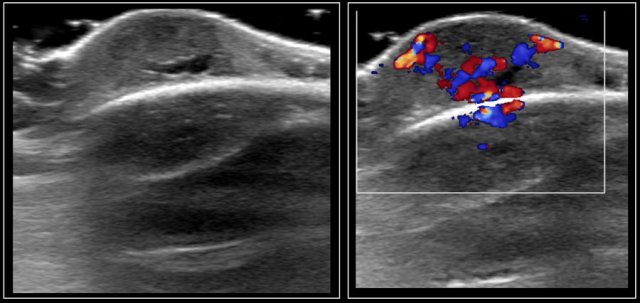

Here an image of a 16-year-old girl with hyperthreoidism.

A diffusely enlarged thyroid gland is seen with hyperemia.

The final diagnosis was Graves disease.

In Graves disease the thyroid gland is also enlarged and shows an increased perfusion.

On color Doppler it has been described as an inferno in red and blue.